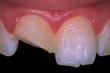

שן קבע שנעקרה ממקומה בתאונה

החדירו מחדש את השן למקומה בזהירות רבה וגשו מייד לרופא השיניים